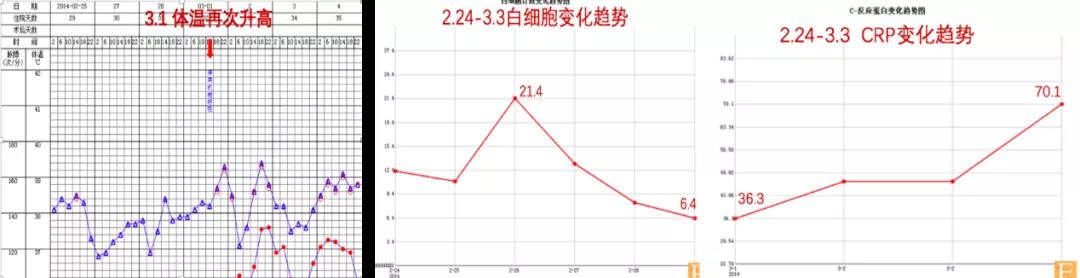

痰培养多次复查均为耐碳青霉烯的鲍曼不动杆菌;多次血培养均为阴性;心脏超声未有瓣膜赘生物发现。2月26日再次调整抗生素方案:停泰能针,改为舒普深针3.0 g静滴q8h;伏立康唑片改为针剂200 mg静滴q12h;加用斯沃针600 mg静滴 q12h治疗。患者体温仍有反复,但血象及C反应蛋白却无明显升高(图6)。

图6. 2月25日至3月3日体温及炎症指标变化